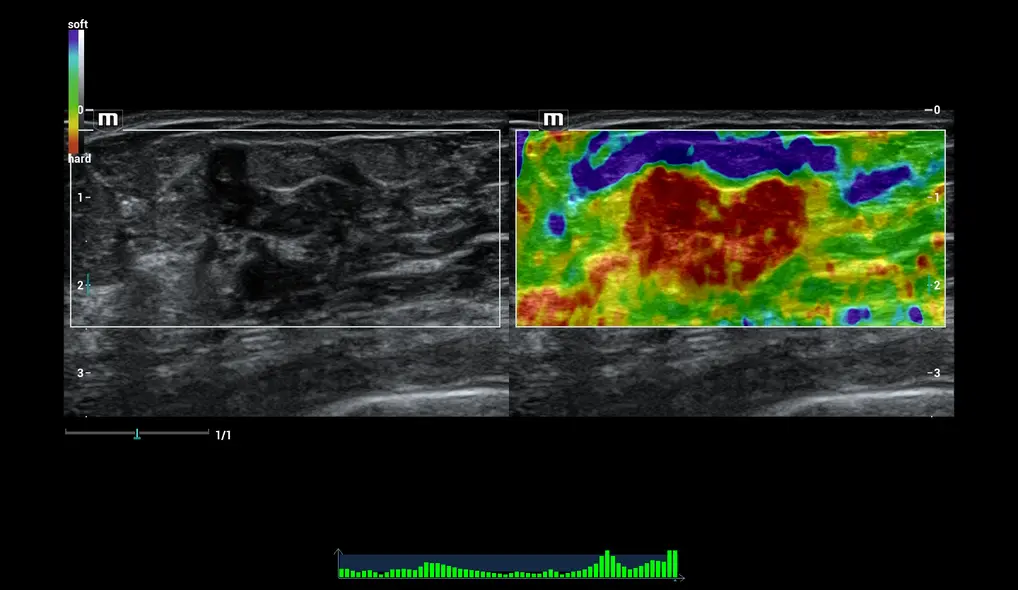

- Эластография сдвиговой волны

Диагностика заболеваний молочной железы Smart Breast

Resona I9 позволяет проводить интеллектуальный анализ молочной железы по шкале BI-RADS, включая полностью автоматическое обнаружение, измерение, аннотирование, анализ поражений, составление отчётов. Протокол ориентирован на очаги поражения, что повышает контроль качества. Множественные поражения могут исследоваться в нескольких плоскостях для получения более полных данных.

Эластография опухоли молочной железы